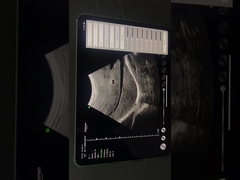

Wuxi Biomedical Technology Co., Ltd.

جودة المحمولة الموجات فوق الصوتية سكانر, الماسح الضوئي بالموجات فوق الصوتية المحمولة manufacturer from China